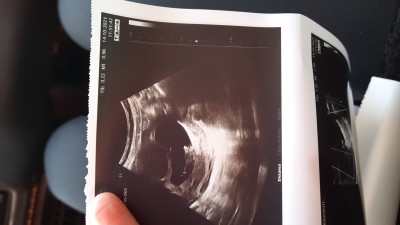

Nuba göre bakar mısınız bilenler 9 haftalıktı usg

Bence erkek bebeğin canim

Çünkü benim bebeğimin de plasentası fasulye şeklindeydi kafası da sağa dönüktü ve vücuduna göre çok daha büyük duruyordu.